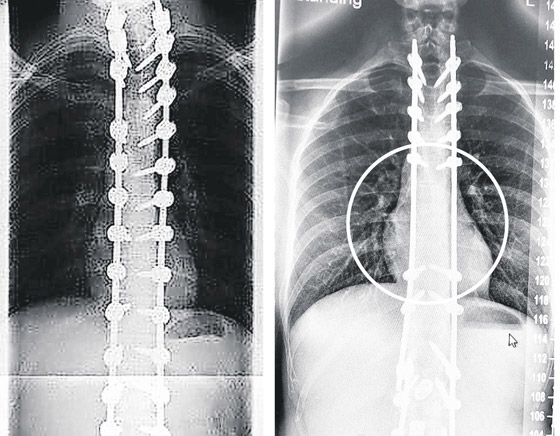

أكد تحقيق موسع أن العشرات من المرضى الذين خضعوا لعمليات جراحية أجراها طبيب جراح في بريطانيا أصيبوا بأضرار بالغة، بسبب وضع مسامير بطريقة خاطئة في ظهورهم. فقد فتح هذا التحقيق بتكليف من مستشفى سالفورد الملكي عام 2021 وأجراه جراحون وخبير مستقل، حيث راجعوا الرعاية التي تلقاها 130 من مرضى ويليامسون، بين عامي 2009 و2014، ووجدوا أن 23 منهم وضعت لهم مسامير في مكانها غير الصحيح في العمود الفقري، وأن خمسة فقدوا كميات زائدة من الدم أثناء الجراحة؛ وأنه في 35 حالة وقعت ممارسة جراحية خاطئة أثناء العمليات.

وضع مسامير بطريقة خاطئة بظهور مرضاه! أخطاء كارثية لجراح بمستشفى بريطاني عريق صورة رقم 1